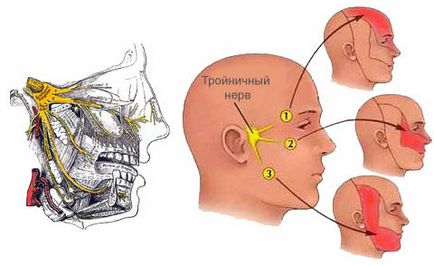

Prosoponeuralgia

Целта на тригеминалния нерв е да осигури чувствителността на човек. Често, след инцидента, битка или други травматични ситуации могат да възникнат невралгия. Тъй като е много силна болка в зъбите, а не на определено място и, като правило, от едната страна на челюстта.

Зъбобол е така типични и атипични. Типично -Време отшумява и дава облекчение на пациента, и започва като токов удар, който се усилва в рамките на няколко секунди, минути, и след това да се пусне. Когато нетипичен невралгия пациент не получи почивка, лечение на това заболяване е много трудно.

Началото на болката може да предизвика дори леко докосване на лицето или прилагането на грим. Ако причината за зъбна болка е невралгия, нужда от помощ невролог. Въпреки това, да се лекува това заболяване рядко работи.